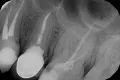

В середине ноября у меня разболелся зуб - верхняя правая 5-ка. Боль тупая, ноющая, иногда с ощущением распирания. Поставили диагноз пульпит, удалили нерв. Но после лечения оставалась легкая боль при накусывании, в январе зуб начал также реагировать на перкуссию. Я посетила консультацию у другого врача, сделала рентген. Мне сказали, что зуб запломбирован нормально, это может быть просто реакция организма на переохлаждение. Со времени той консультации прошел месяц, боль не ушла, зуб стал реагировать на горячее ощущением распирания. Еще иногда я замечаю неприятный привкус, идущий из пространства между этой 5-кой и 6-ой, как будто там что-то гниет.

На мой взгляд, зуб пролечен хорошо, но для полной картины и оценки необходим К/Т (трехмерный снимок). Все симптомы говорят о периодонтите.